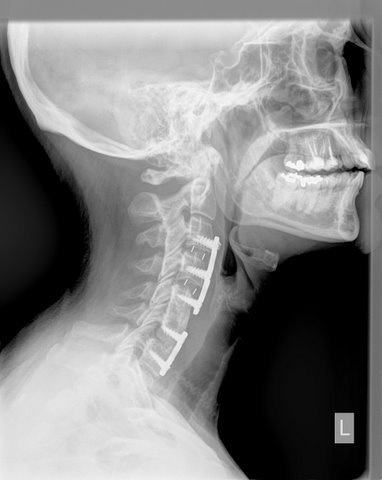

In 2005, Annette had the first of three cervical (neck) spine surgeries resulting in permanent nerve damage, arthritis, and facet disease in her neck.